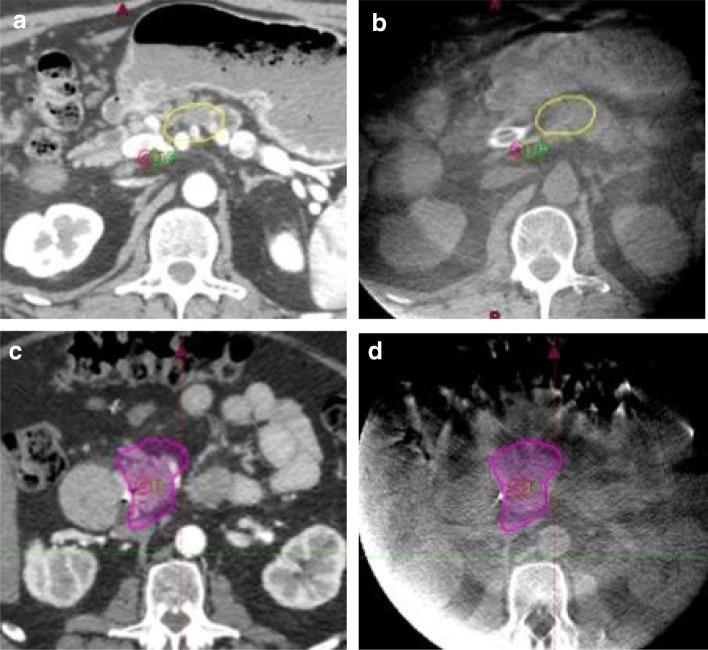

Standard doses of conventionally fractionated radiation have had minimal to no impact on the survival duration of patients with locally advanced unresectable pancreatic cancer (LAPC). The use of low-dose stereotactic body radiation (SBRT) in 3- to 5-fractionshas thus far produced a modest improvement in median survival with minimal toxicity and shorter duration of treatment, but failed to produce a meaningful difference at 2 years and beyond. A much higher biologically effective dose (BED) is likely needed to achieve tumor ablation The challenge is the delivery of ablative doses near the very sensitive gastrointestinal tract. Advanced organ motion management, image guidance, and adaptive planning techniques enable delivery of ablative doses of radiation (> = 100Gy BED) when more protracted hypofractionated regimens or advanced image guidance and adaptive planning are used. This approach has resulted in encouraging improvements in survival in several studies. This review will summarize the evolution of the radiation technique over time from conventional to ablative and describe the practical aspects of delivering ablative doses near the GI tract using cone beam CT image (CBCT) guidance and online adaptive MRI guidance.

标准剂量的常规分割放疗对局部晚期不可切除胰腺癌(LAPC)患者的生存时间几乎没有影响。低剂量立体定向体部放疗(SBRT)在 3-5 次分割中的应用迄今已使中位生存期略有改善,毒性最小,治疗时间缩短,但在 2 年及以后并未产生有意义的差异。需要更高的生物有效剂量(BED)才能实现肿瘤消融。挑战在于在非常敏感的胃肠道附近提供消融剂量。先进的器官运动管理、图像引导和自适应计划技术可在使用更延长的低分割方案或先进的图像引导和自适应计划时提供消融剂量的放疗(> = 100Gy BED)。这种方法已导致几项研究中生存的可喜改善。本综述将总结随着时间的推移,放疗技术从常规到消融的演变,并描述在胃肠道附近使用锥形束 CT 图像(CBCT)引导和在线自适应 MRI 引导来提供消融剂量的实际方面。